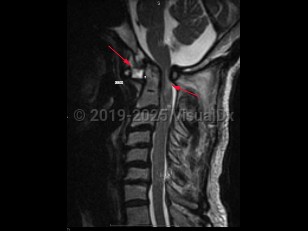

Imaging Studies image of Atlantoaxial instability - imageId=7887372. Click to open in gallery.  caption: '<span>Sag T2 MRI sequence  demonstrates atlantoaxial instablity/dislocation in a patient with  Down syndrome. Note that the atlantoaxial interval is widened  measuring up to 9-10mm and that there is compressive myelopathy of the  spinal cord secondary to narrowing of the spinal canal.</span>'

Sag T2 MRI sequence demonstrates atlantoaxial instablity/dislocation in a patient with Down syndrome. Note that the atlantoaxial interval is widened measuring up to 9-10mm and that there is compressive myelopathy of the spinal cord secondary to narrowing of the spinal canal.